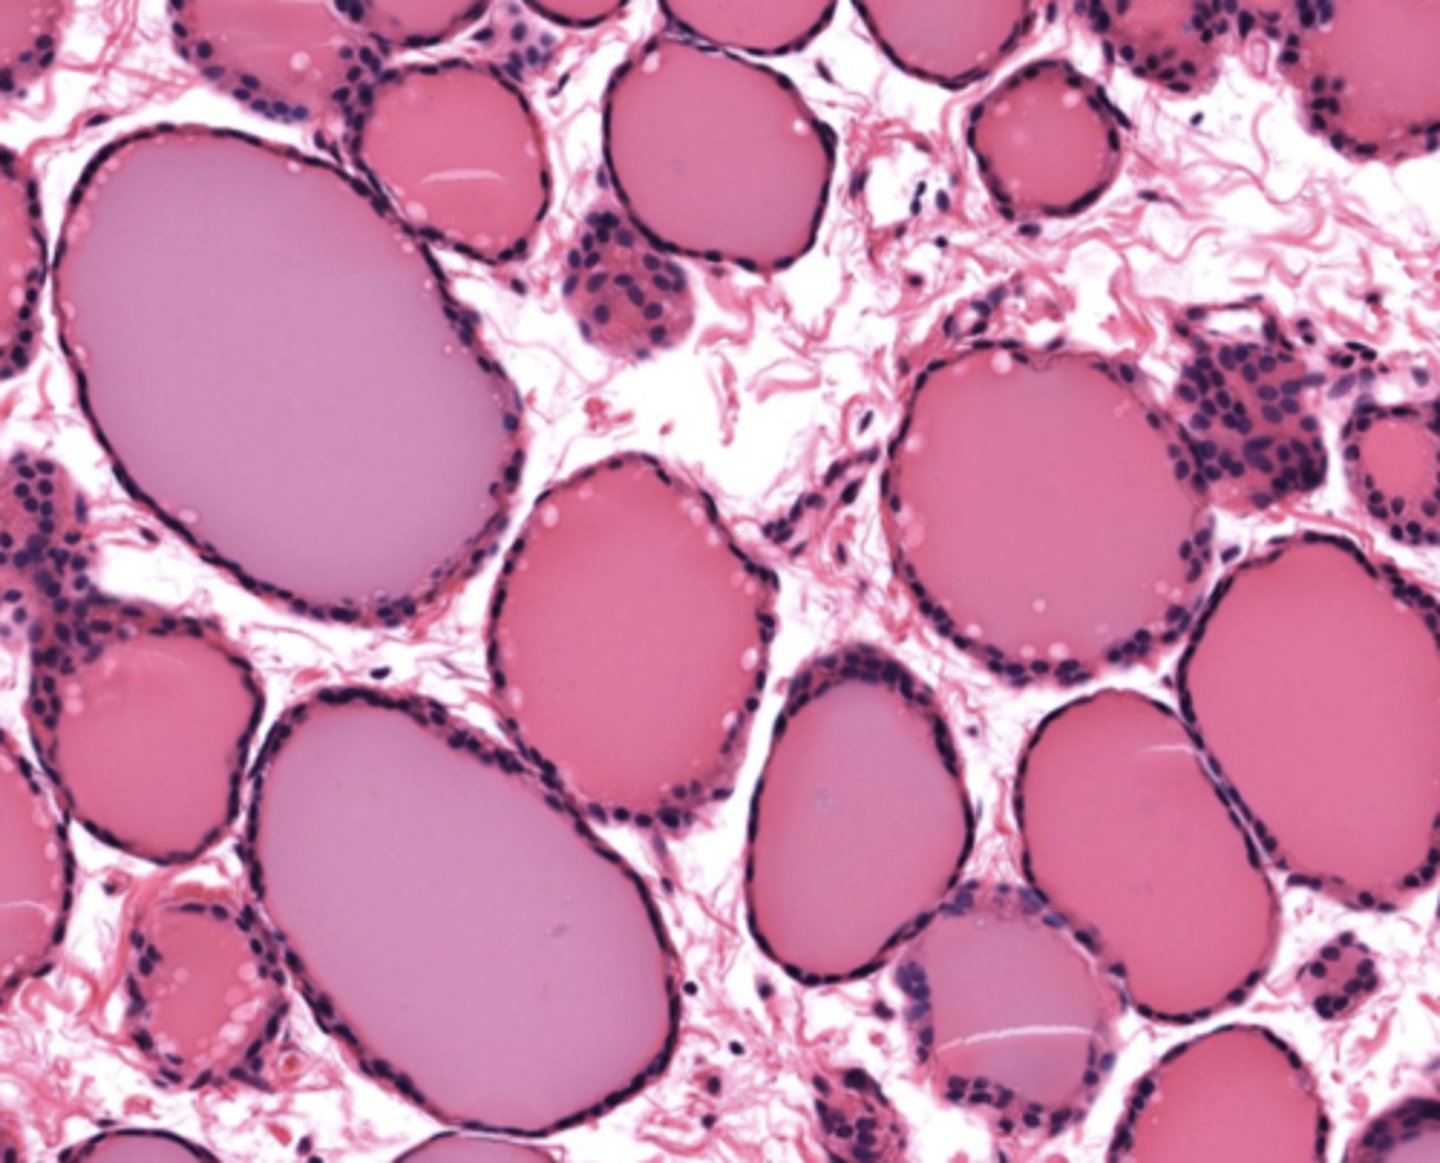

Thyroid gland

Colloid-filled follicle

Follicular cell